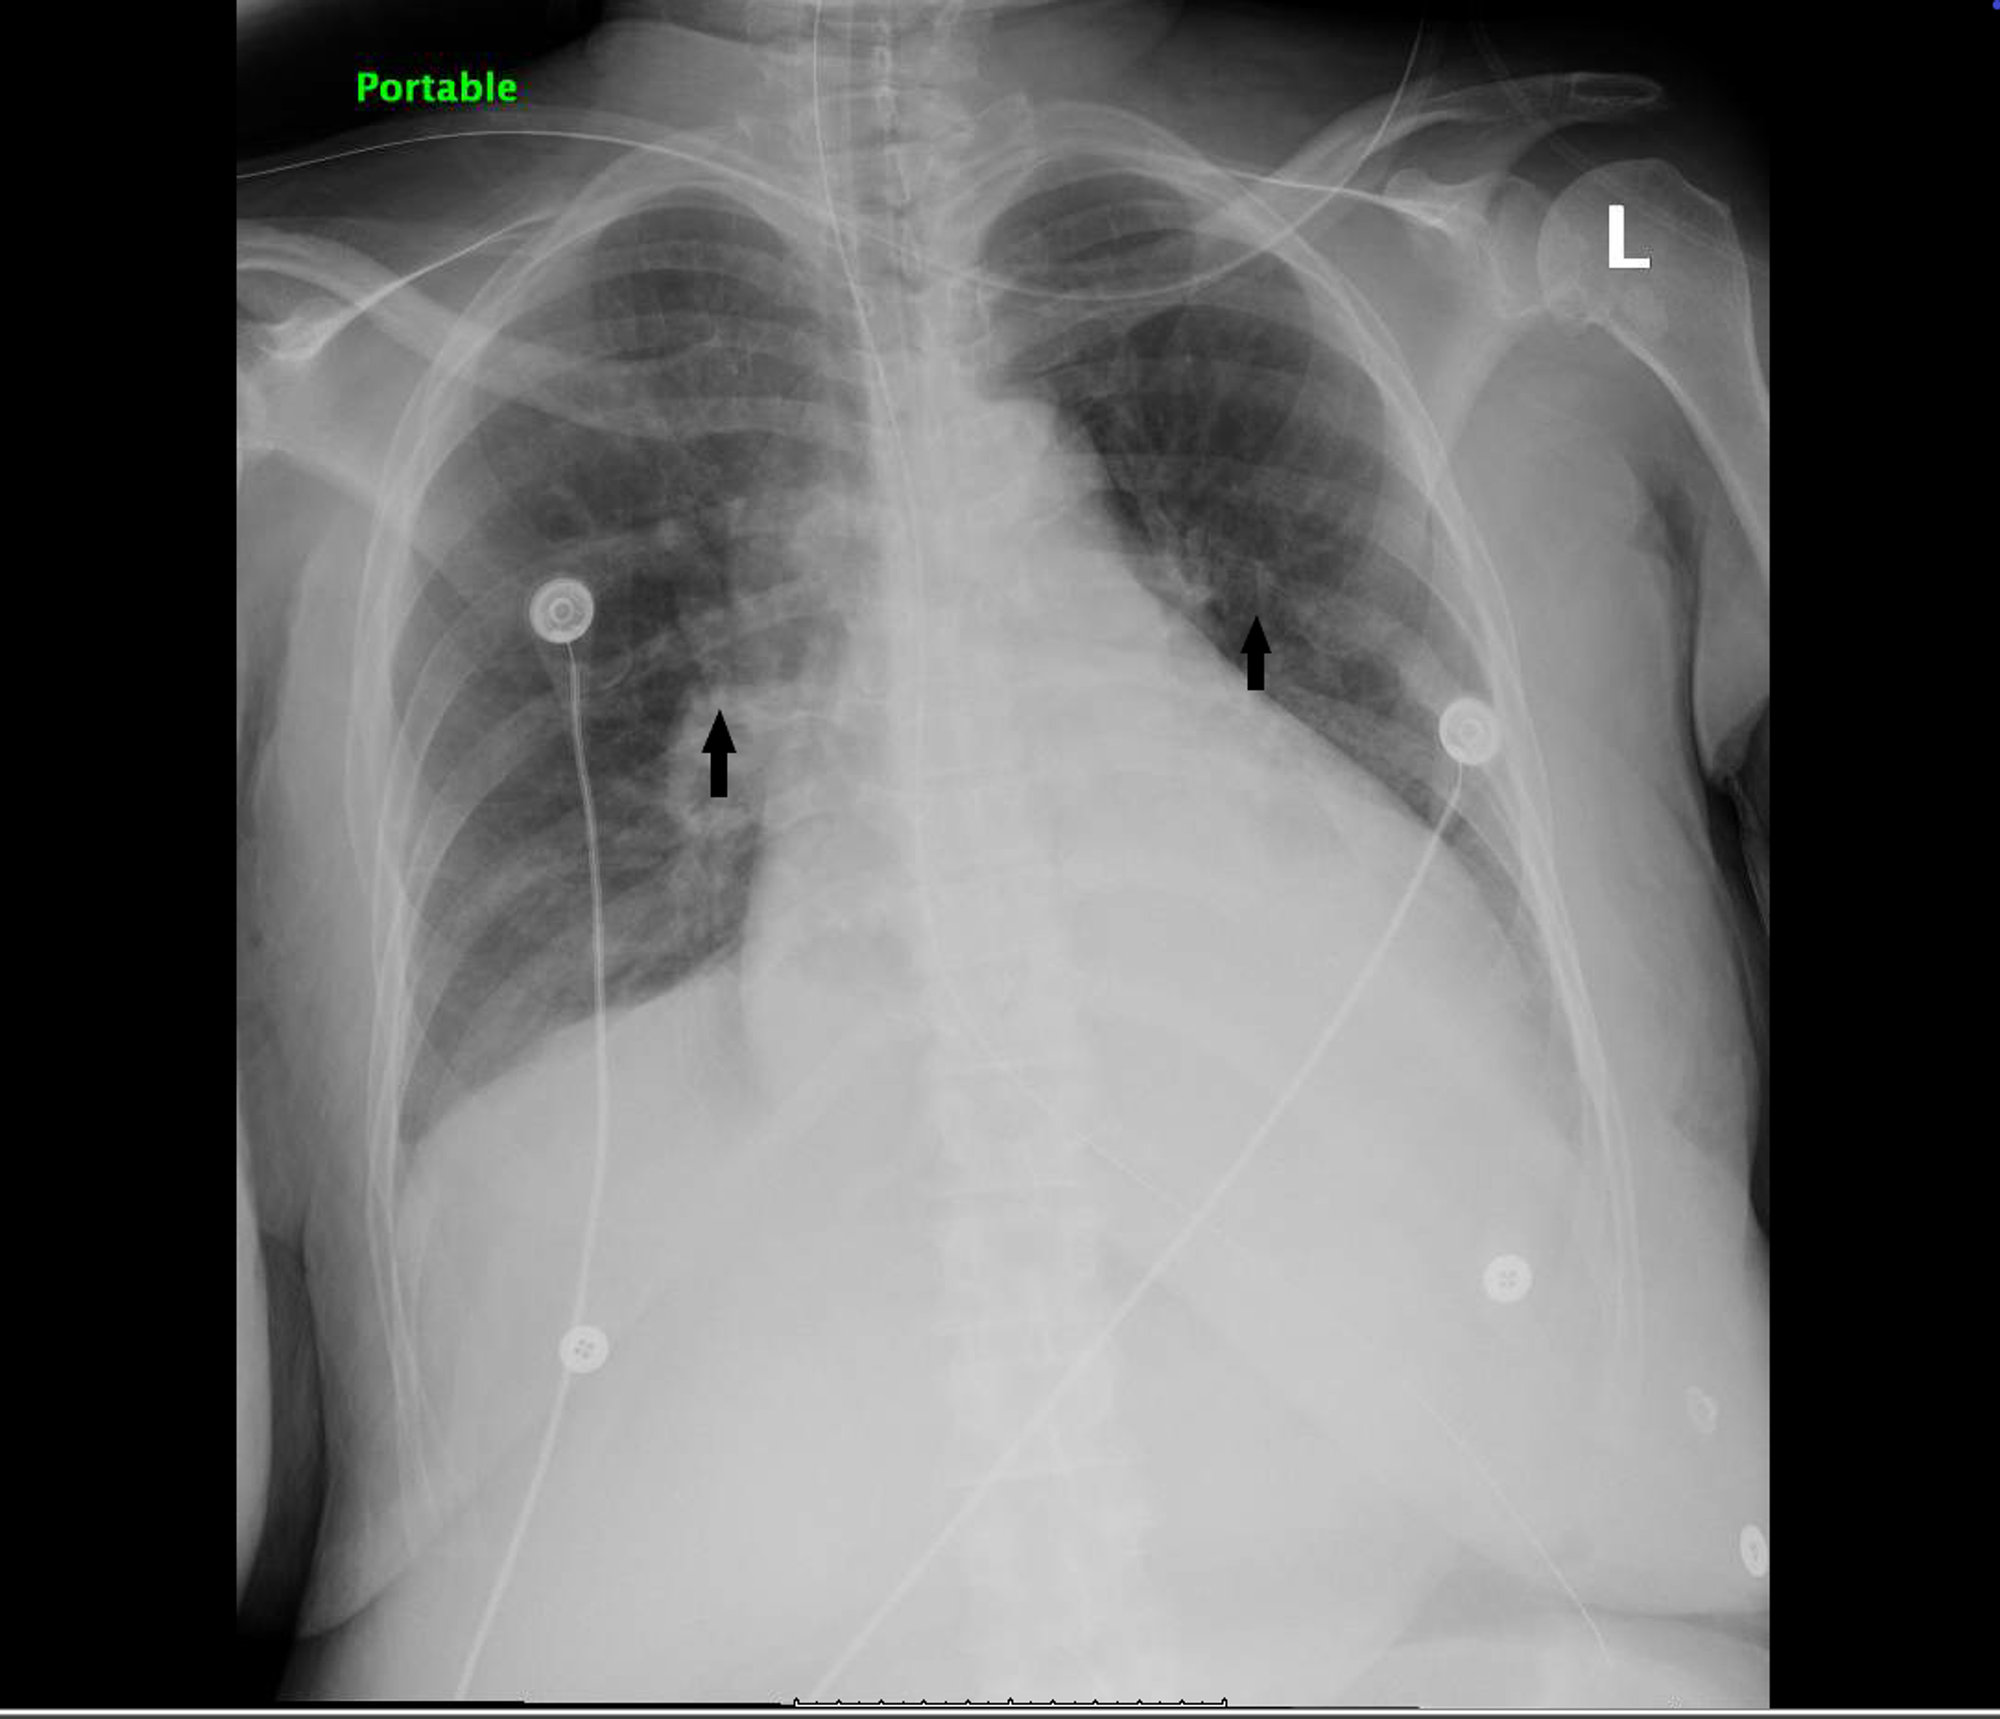

Chest Xray showing bilateral interstitial infiltrates (arrows What Are Bilateral Infiltrates On Chest X Ray lung infiltrates refer to substances, such as fluid or cells, that fill the lung, appearing denser on medical imaging. detecting diffuse lung infiltrates on chest radiography is a common clinical problem. from a pathophysiological perspective, the term infiltrate refers to “an abnormal substance that accumulates gradually. classically, viral pneumonias demonstrate bilateral, diffuse, and interstitial infiltrates, while. What Are Bilateral Infiltrates On Chest X Ray.